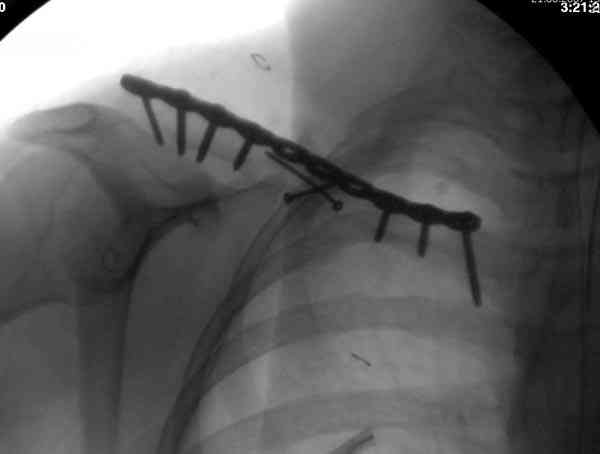

Судя по проекциям ключицы, очевидно разобщение фрагментов, чаще всего сопровождающееся интерпозицией платизмой. для 15 летнего пациента, категории физически активных пациентов выбрал бы оперативный метод( интрамедуллярно

винтом с частичной резьбой).

При оперативном лечении ключицы необходимо применить методику Inderect Reduction Technique с обнажением кости только с той стороны, где устанавливается пластина.

При применении спиц из-за неудобного вектора один из фрагментов необходимо приподнять от грудной клетки и, тем самым, приподнимая ухудшают, заднее кровеснабжение.

Спицы противопоказаны не только из-за отсутствия стабильности, также из-за их опасной миграции. Описаны много случаев миграции спиц даже в каротидную артерию.